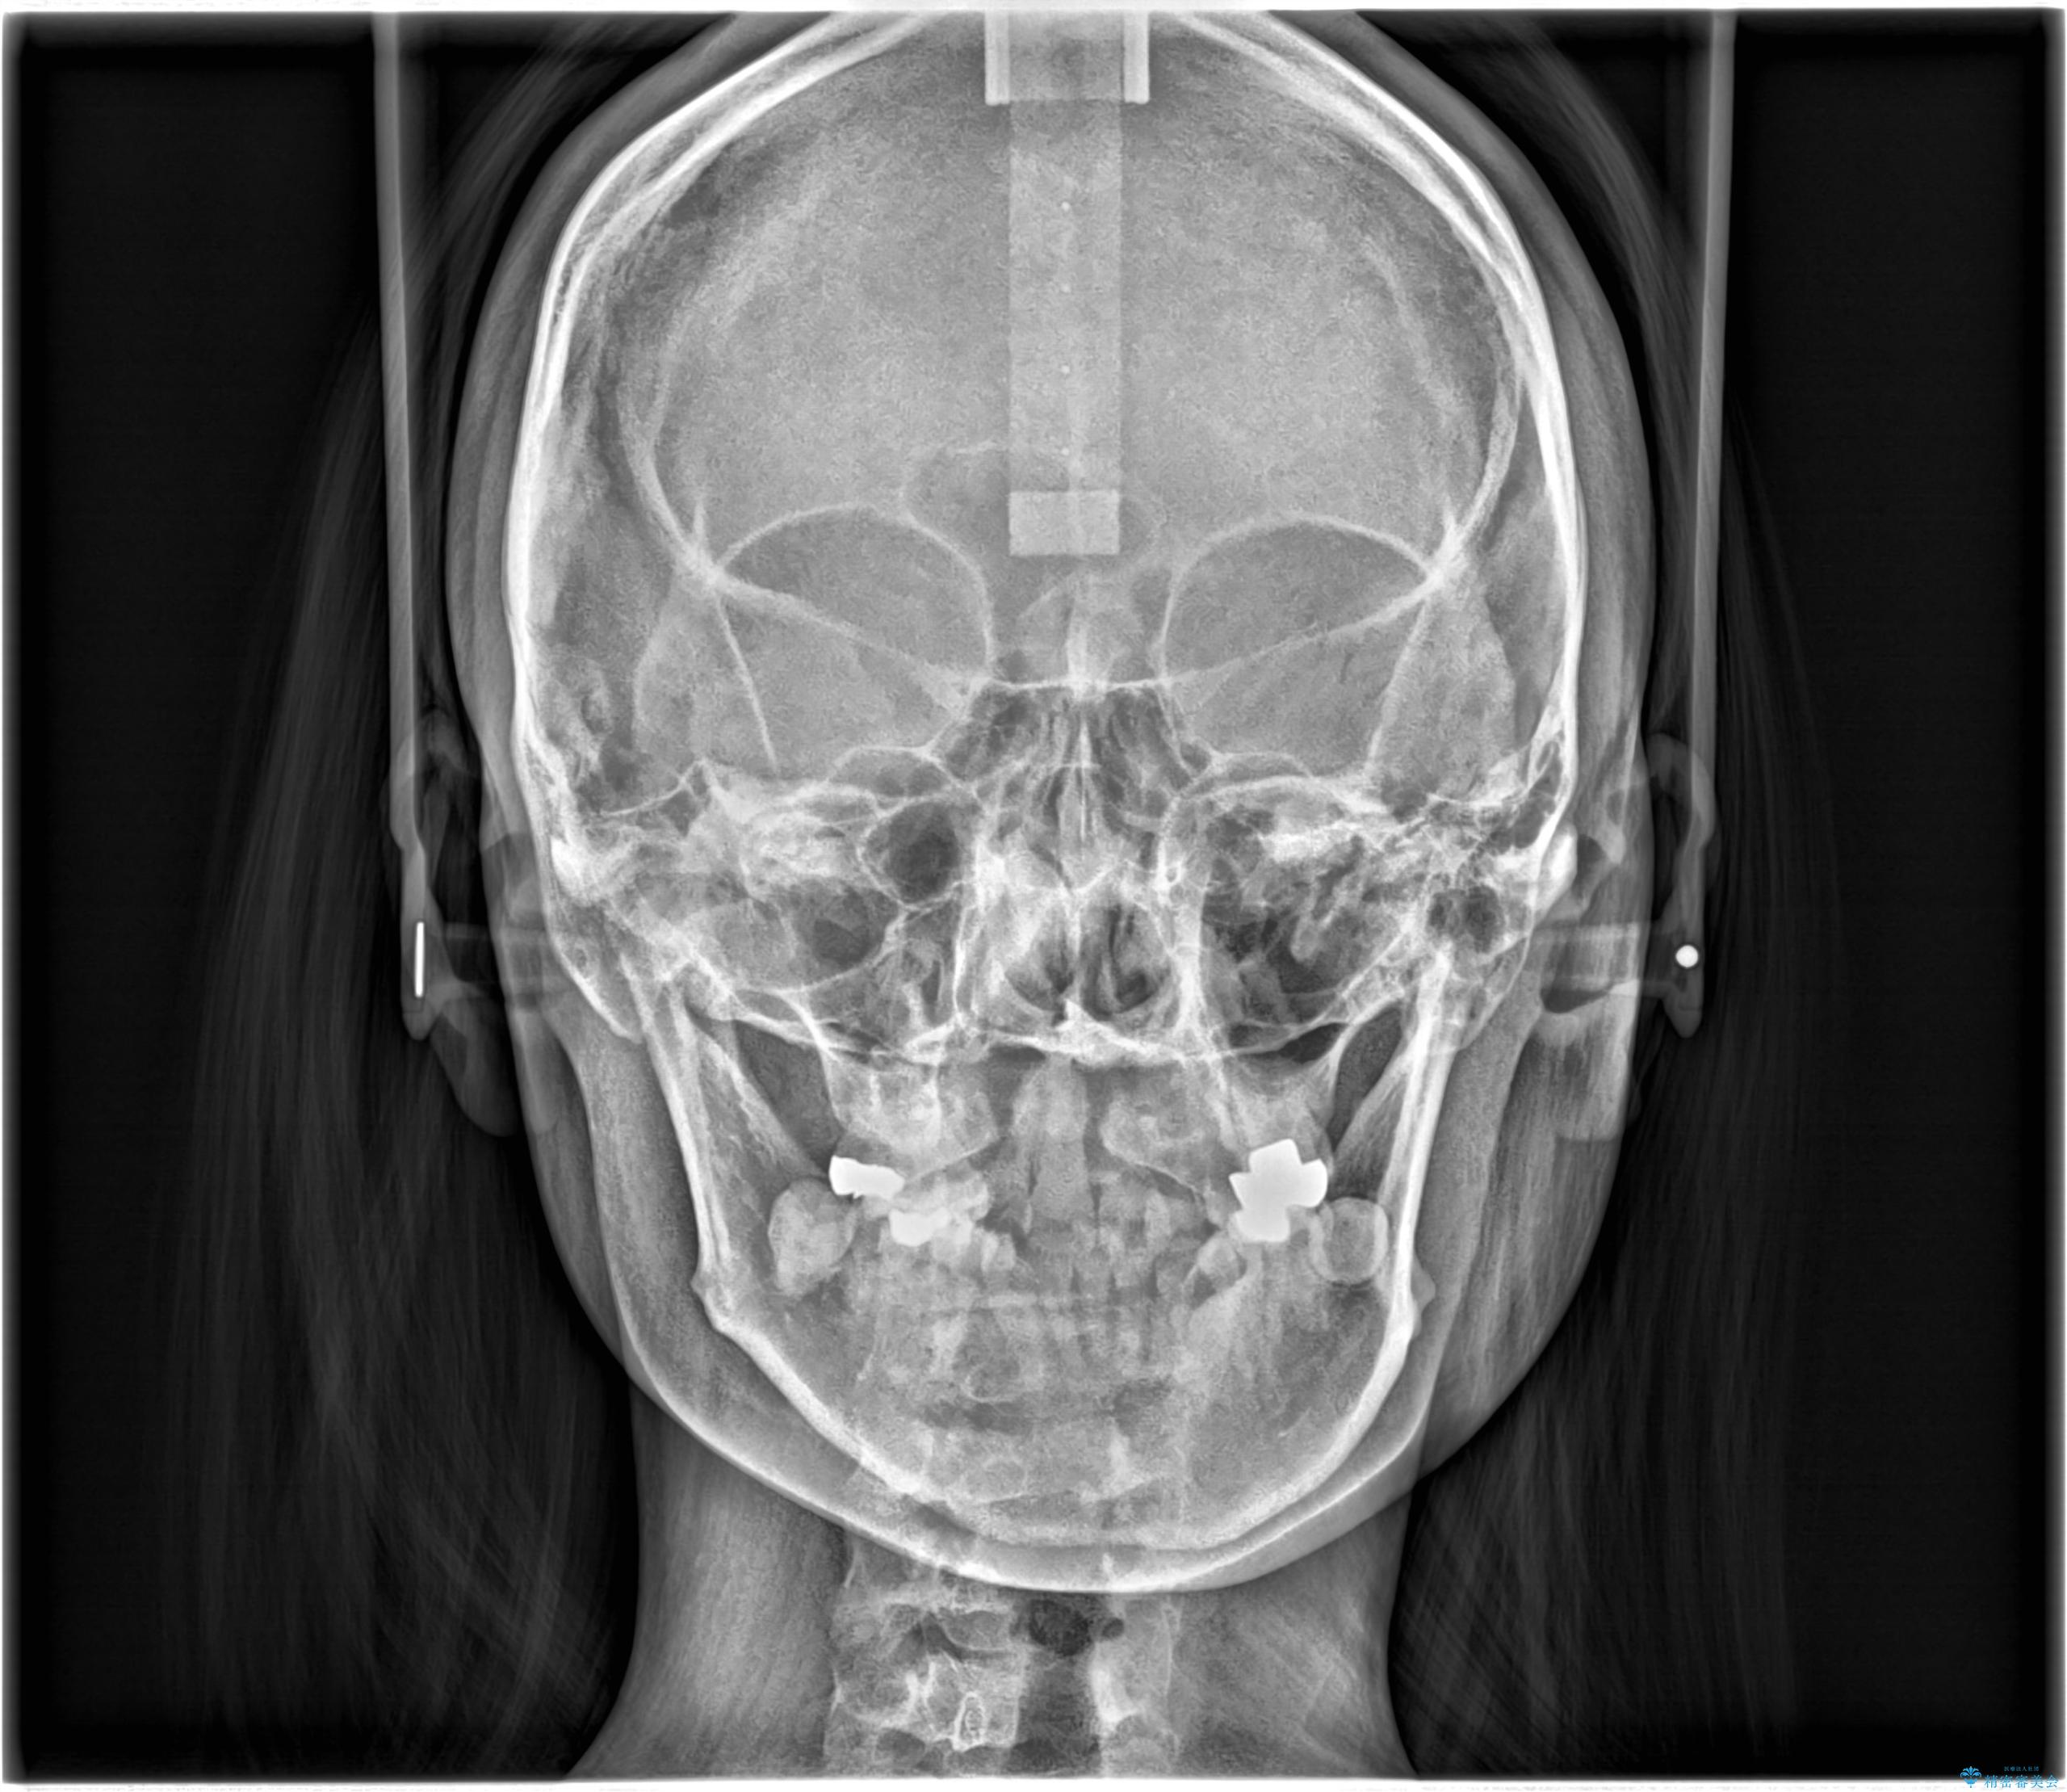

骨格的顎の変位を認めたため、顔貌に対しピッタリ上下の歯の正中を合わせることは難しいと説明し、上下左右計4本小臼歯を抜歯しワイヤー矯正治療を行いました。

- 主訴:口元を下げて前突感を無くしたい、下の歯の凹凸も無くしたい

右側第二小臼歯、左側第一小臼歯、下顎両側第一大臼歯を抜歯しワイヤ-矯正を行いました。